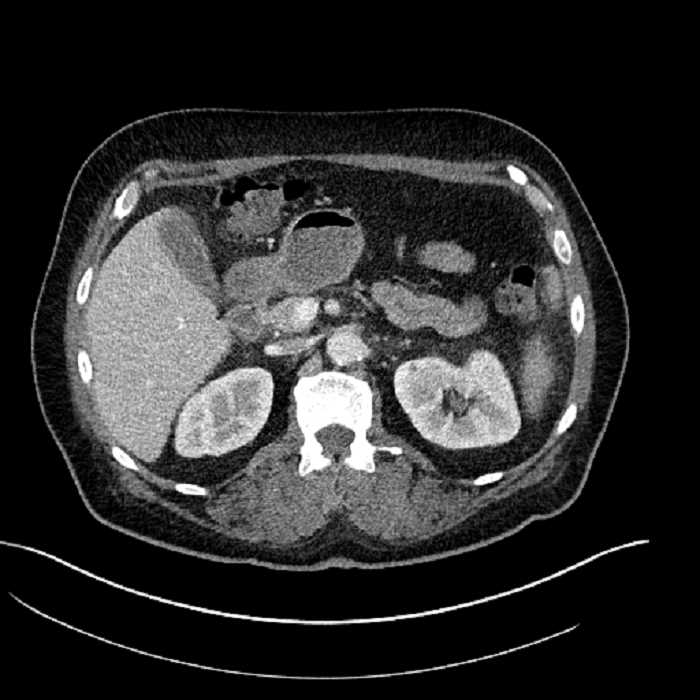

Age: 63

Sex: Male

Indication: Abdominal pain

• Large fluid density structure in hepatic segments 7 and 8 measuring 10 x 7 x 7 cm with internal septation and circumferential ill-defined low density compatible with edema

• Peripherally enhancing subcapsular collections along the anterior margin of the left hepatic lobe measuring 3 x 1 cm and 2 x 1 cm

• Clearly marginated fluid density structure in segment 7 and several other scattered tiny hypodensities, which likely represent cysts

• Hepatic abscess

Acute sigmoid diverticulitis complicated by a small contained perforation and a large abscess in the right hepatic lobe. Additional small subcapsular abscesses along the anterior margin of the left hepatic lobe.

• The classic CT imaging appearance is a double target sign with internal low density surrounded by an internal enhancing rim (capsule) and a low density external rim (edema)

Hepatic abscess showing the double target sign with low density internally surrounded by a thin inner enhancing rim (red arrow) and ill-defined outer low density rim (yellow arrow). Blue arrow indicates an internal septation. Red arrows: additional smaller subcapsular abscesses. Red arrow: focal contained perforation associated with diverticulitis.